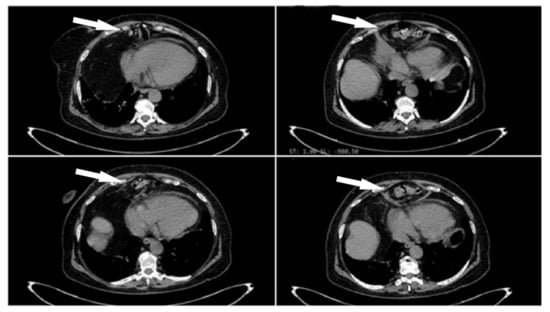

2. Case Presentation